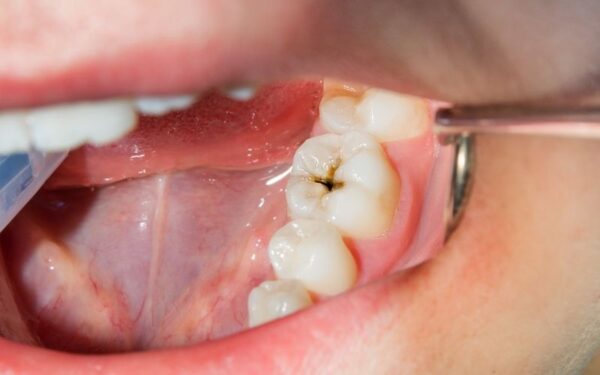

Sâu chân răng là tình trạng sâu răng xuất hiện ở bề mặt chân răng – vùng tiếp giáp trực tiếp với nướu răng, khiến chân răng bị đen và tổn thương. Nếu không được phát hiện và điều trị kịp thời, sâu chân răng có thể dẫn đến nguy cơ hỏng tủy, gây viêm nhiễm và thậm chí mất răng vĩnh viễn.

- Màu răng thay đổi từ vàng, nâu sang đen – dấu hiệu sâu chân răng đã ăn vào tủy.

Giai đoạn 2: Sâu chân răng đã hình thành lỗ sâu – Trám răng bảo vệ chân răng

Khi sâu chân răng đã phát triển mạnh, tạo thành các lỗ hổng rõ ràng ở chân răng hoặc thân răng kèm theo những đốm đen sẫm màu, việc can thiệp điều trị bằng trám răng là cần thiết. Bác sĩ tại Nha khoa Sài Gòn sẽ tiến hành làm sạch vùng sâu, loại bỏ mô răng bị tổn thương và sử dụng vật liệu trám chuyên dụng để lấp đầy các lỗ sâu. Phương pháp trám răng giúp ngăn ngừa vi khuẩn tiếp tục phát triển, bảo vệ cấu trúc răng còn lại và duy trì chức năng ăn nhai bình thường. Trám răng cũng đảm bảo tính thẩm mỹ, giúp răng trông tự nhiên và khỏe mạnh hơn.